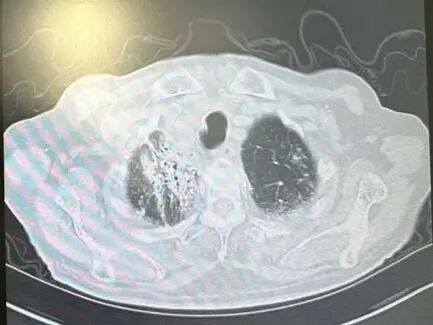

内容提要 近日,市第二人民医院呼吸与危重症医学科宋刚主任团队,成功救治一名98岁高龄、患有罕见隐源性机化性肺炎(COP)的患者。面对高龄、病情复杂、诊治风险高等重重困难,团队凭借精湛医术与丰富经验,帮助老人转危为安,再次彰显了科室在危重症救治领域的强大实力。 挑战一:高龄禁区,敢为人先 患者因发热、咳嗽,伴乏力、气短、喘息等症状来院,此前在当地诊所使用多种抗生素均无效,病因成谜。要明确诊断,支气管镜检查是关键一步,但对近百岁老人而言,此项操作犹如踏入“生命禁区”,风险极高。宋刚主任团队没有退缩,在全面评估、周密预案、充分沟通的基础上,凭借丰富经验成功实施检查,为后续治疗打开了至关重要的突破口。 治疗前患者肺部CT影像 挑战二:罕见病症,迷雾重重 检查结果指向一种罕见疾病——隐源性机化性肺炎(COP)。此病本就少见,好发于50~60岁人群,在近百岁老人中发生更是极为罕见。更为棘手的是,患者还伴有胸腔积液。COP通常表现为发热和肺部影像上的“游走性”阴影,很少合并胸腔积液,这使得诊断工作如雾里看花,难度倍增。 挑战三:病菌分辨,生死抉择 诊断刚明,新的考验接踵而至:患者标本中检出了根毛霉菌。COP的核心治疗是糖皮质激素,若根毛霉菌是致病菌,激素可能引发真菌扩散,用药无疑将导致致命风险。因此,辨别其是“定植菌”还是“致病菌”,成为治疗成败的关键。 宋刚主任团队凭借丰富的临床经验和严谨的诊疗思维,结合患者肺部影像特征、症状及化验结果,综合判断认为该霉菌属于定植菌,从而排除了治疗障碍,确保了后续用药安全。 精心施治,百岁老人转危为安 在后续治疗中,团队如履薄冰,精细平衡抗凝与激素治疗带来的出血、感染等风险,制定个体化方案。经过精心治疗与护理,老人肺部病灶显著吸收,各项指标恢复正常,最终康复出院。 治疗前后肺部CT影像对比,左侧为治疗后,右侧为治疗前。 此次成功救治,充分体现了市二院呼吸与危重症医学科在复杂疑难呼吸道疾病及危重症领域的综合救治能力。面对高龄高风险患者,团队始终以患者为中心,在风险与疗效间精准把握,用技术与责任守护每一位患者的呼吸健康。 人民医院 人民名医 宋刚 主任医师 ·葫芦岛市第二人民医院呼吸与危重症医学科主任 ·辽宁省生命科学学会东北呼吸与危重症医学(PCCM)分会辽宁省基层委员会副主任委员 ·辽宁省细胞生物学学会放射粒子治疗专业委员会理事 ·辽宁省抗击新冠肺炎疫情先进个人 ·辽宁省预防医学会第一届吸烟相关疾病防治专业委员会委员 ·葫芦岛市劳动鉴定委员会专家库成员 ·葫芦岛市医学会呼吸内科学分会第三届委员会副主任委员 专业特色:擅长呼吸系统疑难及急危重患者的救治,如急慢性支气管炎、支气管哮喘、慢性阻塞性肺疾病、肺炎、肺栓塞、肺癌、间质性肺疾病、睡眠呼吸暂停综合征等,尤其擅长有创无创机械通气、支气管镜下相关检查及治疗(TBNA、气道支架置入术、球囊扩张等)、全肺灌洗术等领先技术,发表国家级期刊多篇。 出诊时间:每周二、周四全天 出诊地点:门诊二楼东侧35诊室